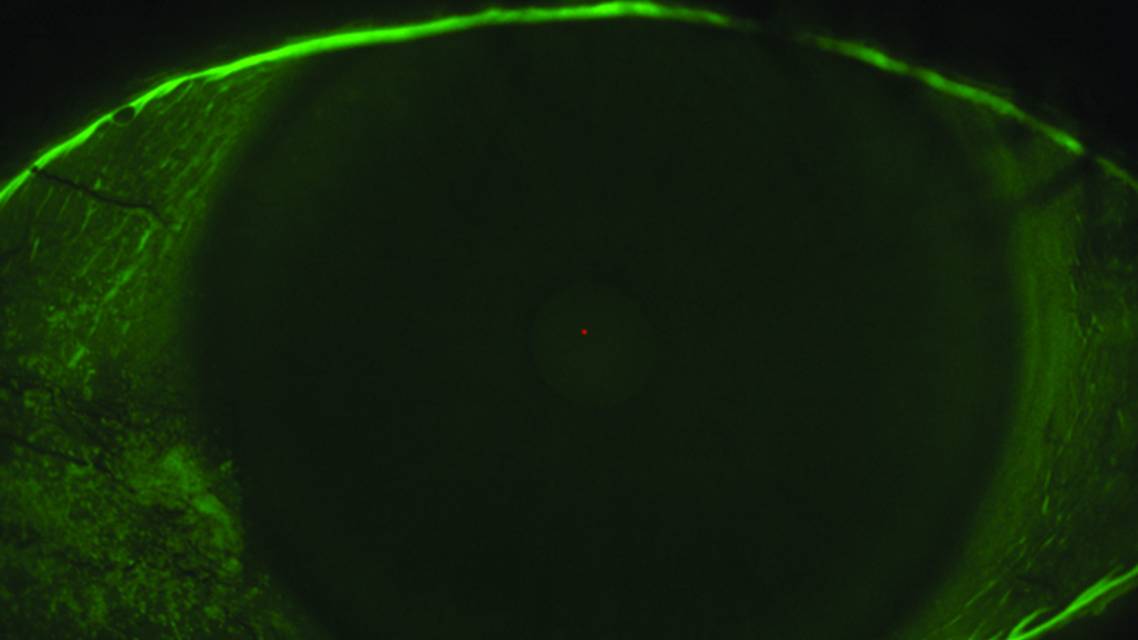

The ocular surface staining component of the diagnosis is characterized by corneal staining with more than five spots of punctate staining with fluorescein, more than nine spots of conjunctival punctate staining with lissamine green, and/or lissamine green staining of the lid margin that is greater than 2 mm in length and at least 25% of the width of the lid margin.